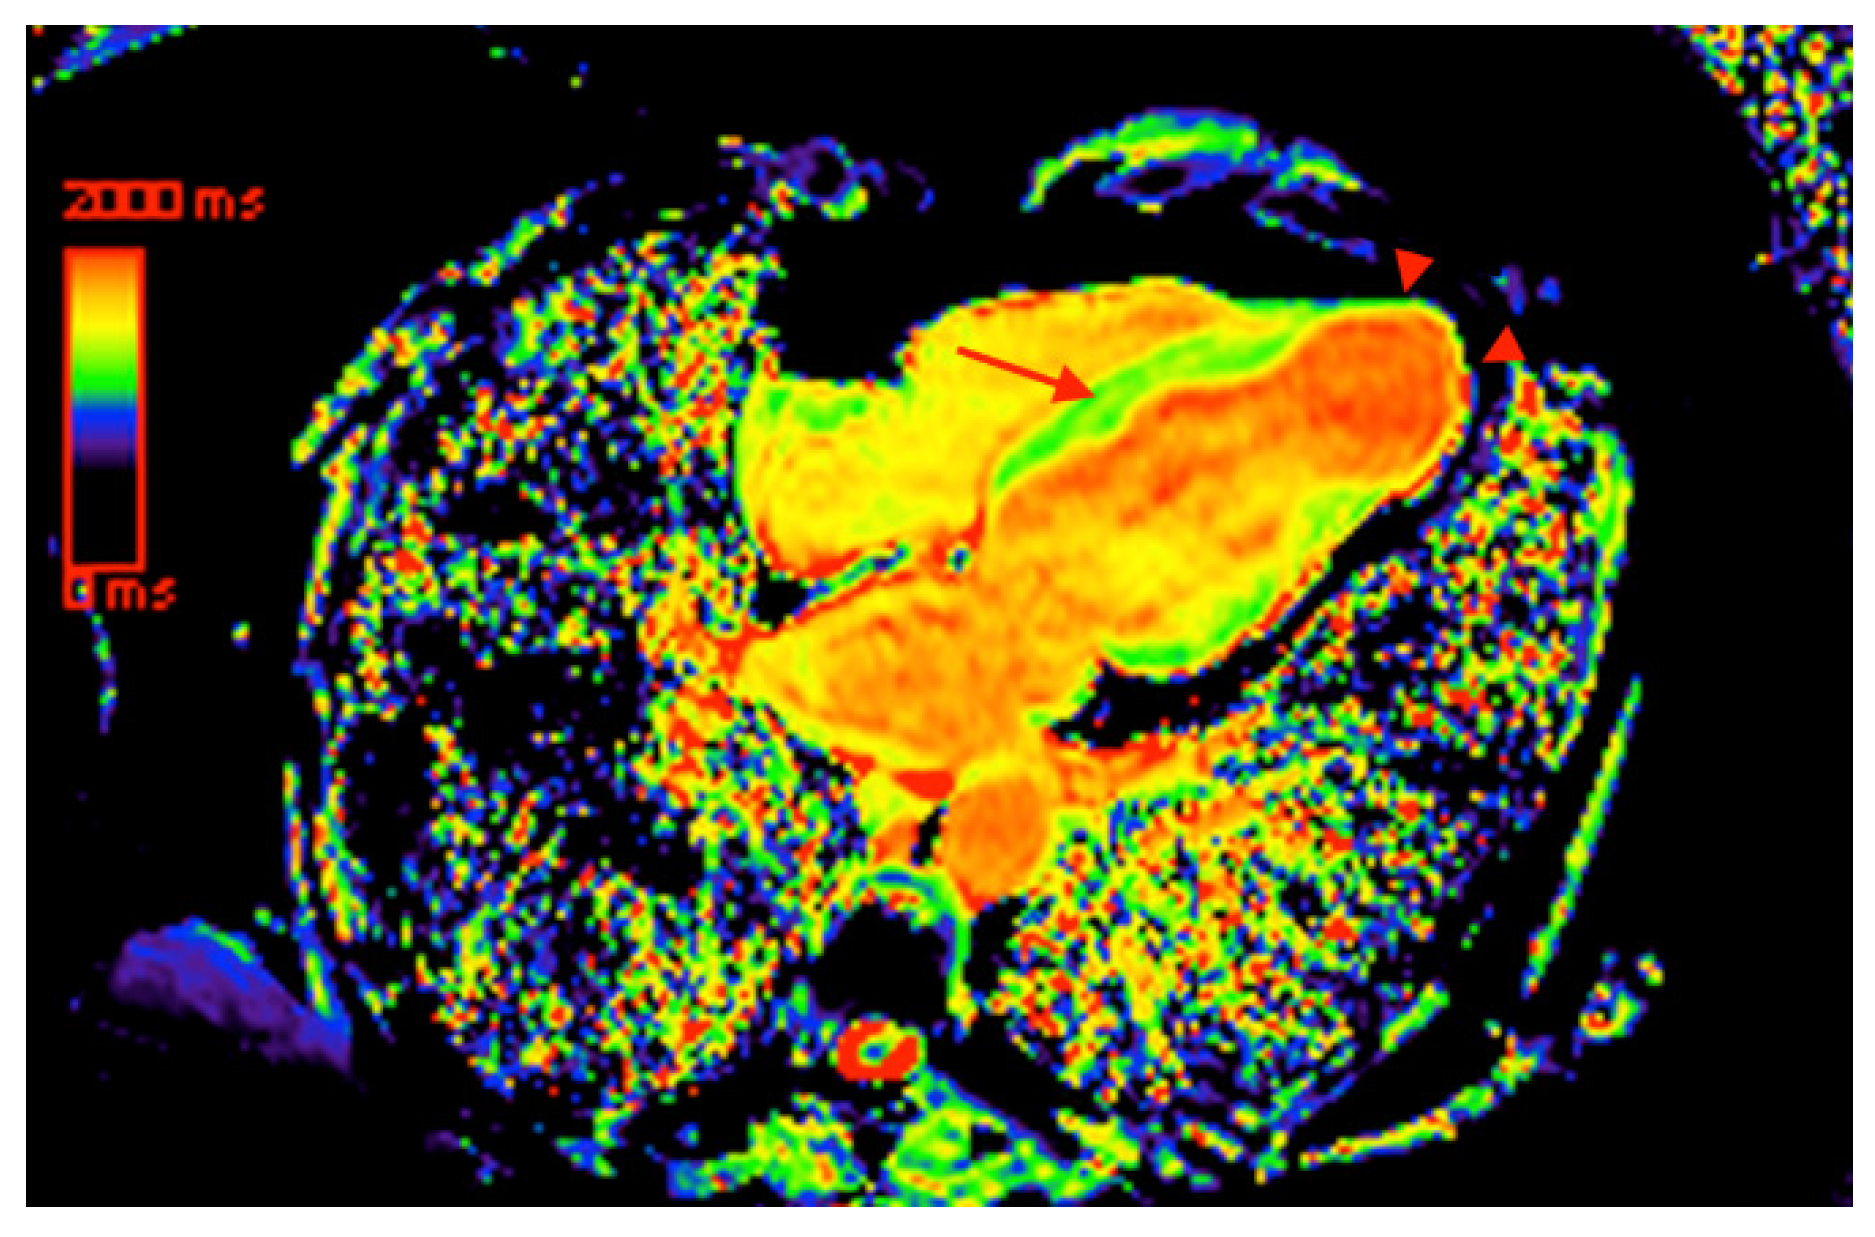

- Torreão, J.A.; Ianni, B.M.; Mady, C.; Naia, E.; Rassi, C.H.; Nomura, C.; Parga, J.R.; Avila, L.F.; Ramires, J.A.; Kalil-Filho, R. Myocardial tissue characterization in Chagas’ heart disease by cardiovascular magnetic resonance. J. Cardiovasc. Magn. Reson. 2015, 17, 97. [Google Scholar] [CrossRef]

- Kammerlander, A.A.; Marzluf, B.A.; Zotter-Tufaro, C.; Aschauer, S.; Duca, F.; Bachmann, A.; Knechtelsdorfer, K.; Wiesinger, M.; Pfaffenberger, S.; Greiser, A. T1 mapping by CMR imaging: From histological validation to clinical implication. JACC Cardiovasc. Imaging 2016, 9, 14–23. [Google Scholar] [CrossRef] [PubMed]